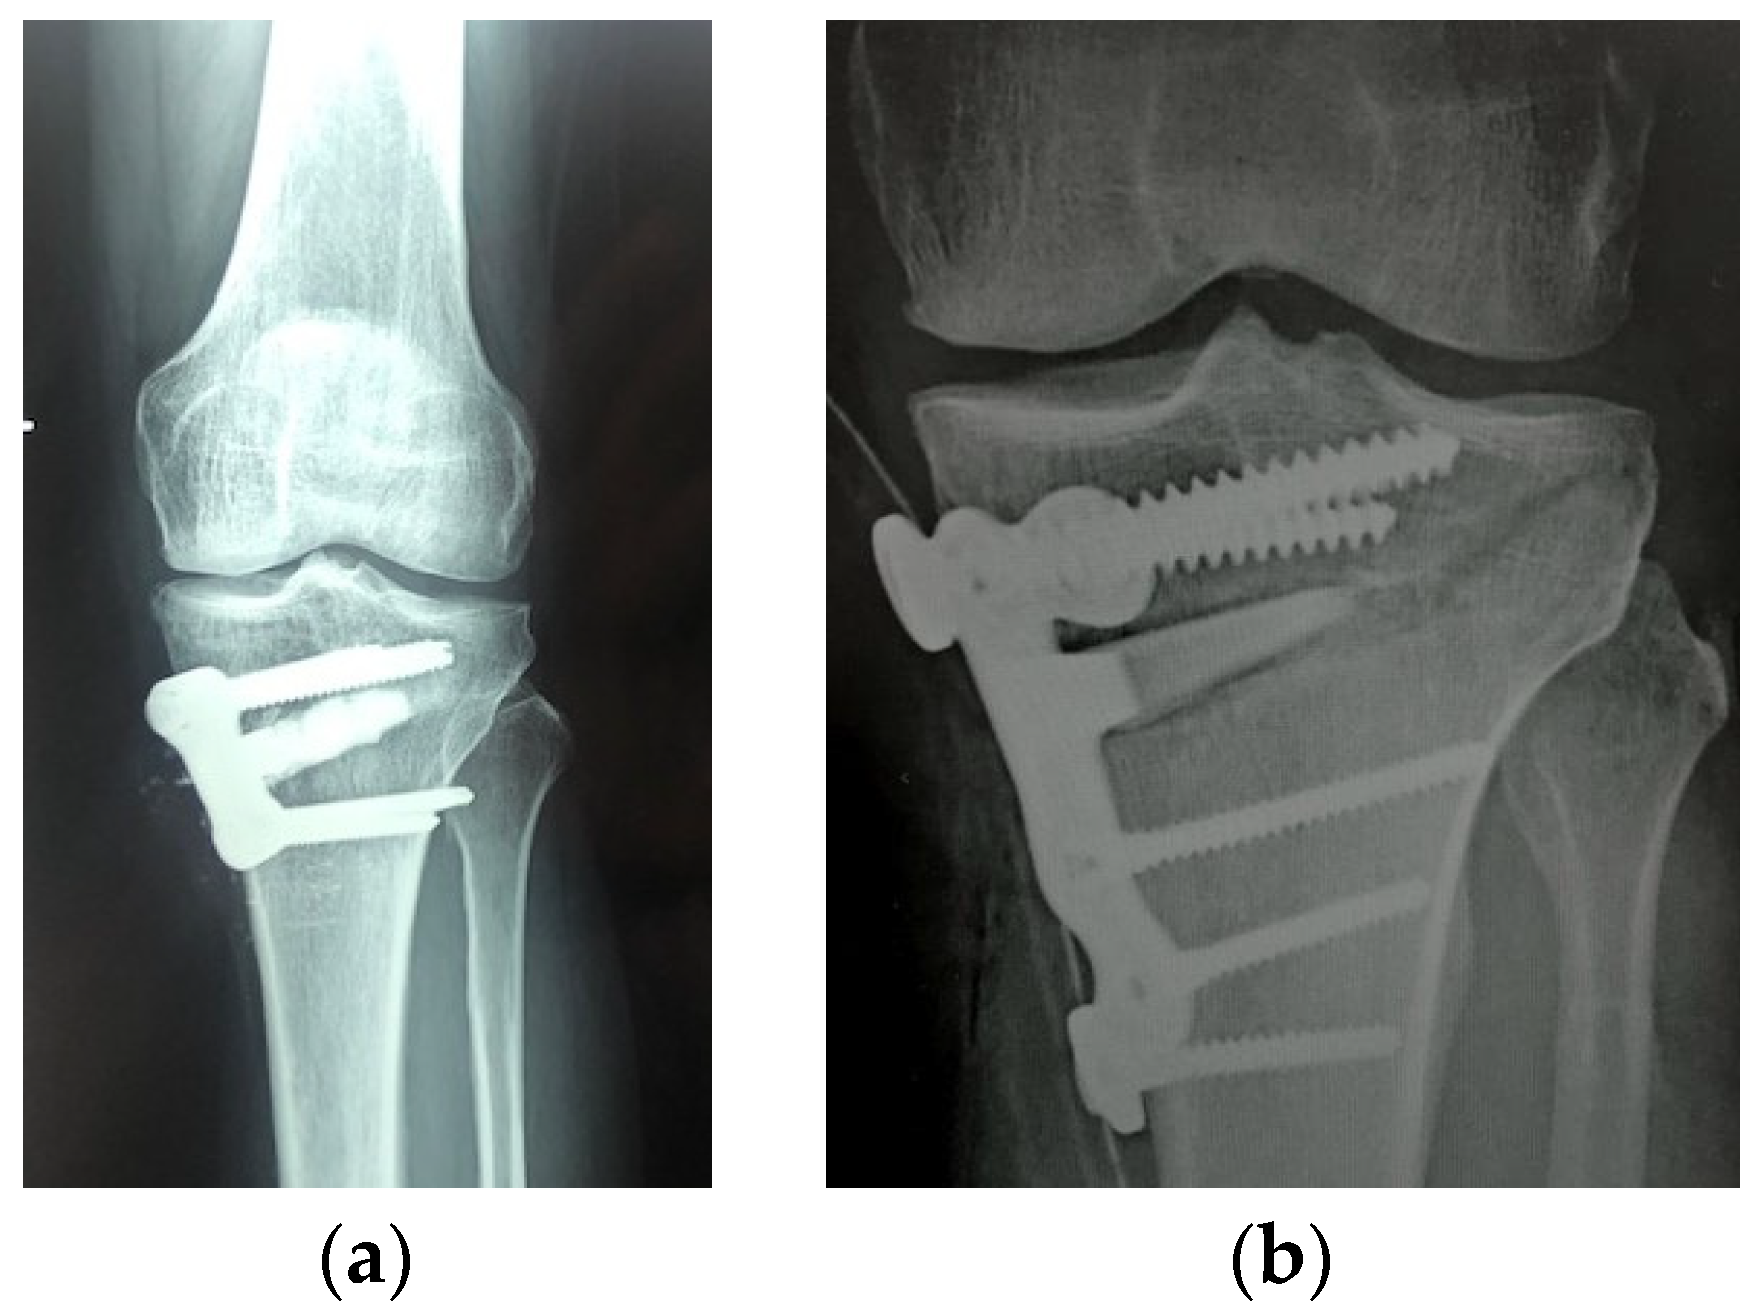

4.1.1. Autografts